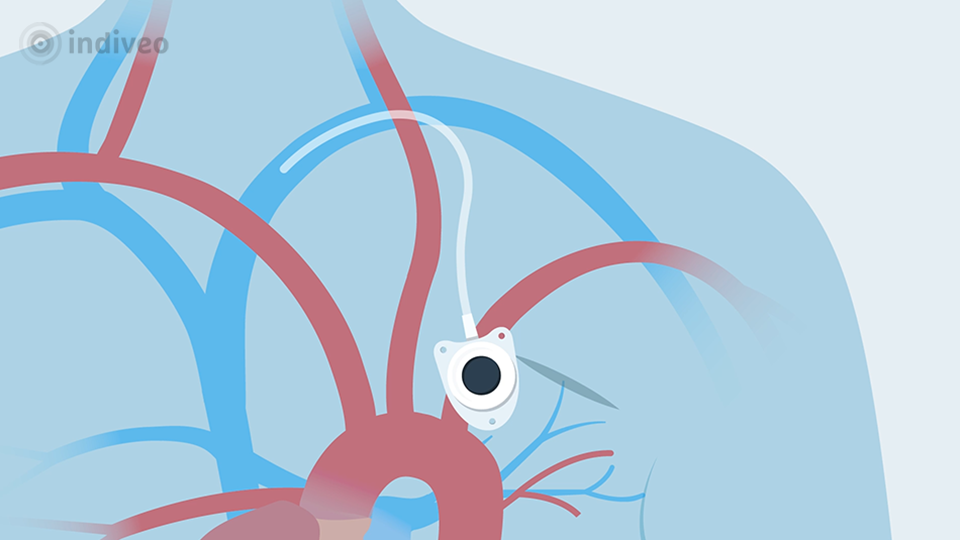

In deze Divi krijgt de patiënt uitleg over wat een port-a-cath is en waarom deze wordt geplaatst. De patiënt ziet dat dit een klein reservoir onder de huid is dat via een slangetje in een bloedvat ligt, waardoor medicijnen of vocht gemakkelijk toegediend kunnen worden en bloed kan worden afgenomen. Ook wordt uitgelegd hoe de plaatsing verloopt, hoe de port-a-cath gebruikt wordt tijdens behandelingen en waar de patiënt op moet letten in het dagelijks leven.